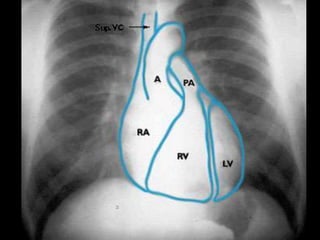

RADIOGRAFIA

• Radiografía normal

• Radiografía patológica

– Ensanchamiento mediastinal

• Técnica radiográfica

• Estructuras normales de tamaño o distribución atípica

• Estructuras vasculares

• Tumores

RADIOGRAFIA • Radiografía normal •Radiografía patológica – Ensanchamiento mediastinal • Técnica radiográfica • Estructuras normales de tamaño o distribución atípica • Estructuras vasculares • Tumores